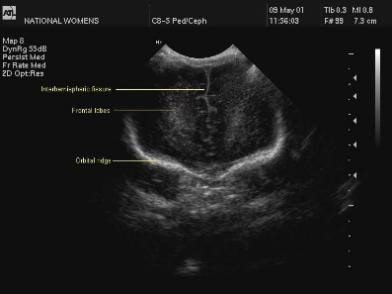

1. Frontal Lobes

Here is an image taken through the frontal lobes. It is possible to see the orbital ridge in the image that forms the inferior boundary.